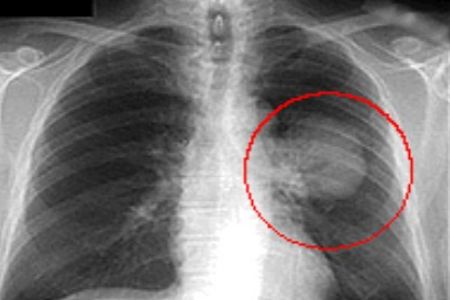

Wanneer een arts op grond van de klachten en de kenmerken van de patiënt meent dat er mogelijk sprake is van longkanker, gebeurt er meestal eerst een radiografie van de borstkas.

Röntgenfoto waarop een tumor zichtbaar is

Daarop volgt dan indien nodig een CT-scan, die onder meer informatie verschaft over de omvang, de uitzaaiing en de kenmerken van de tumor.